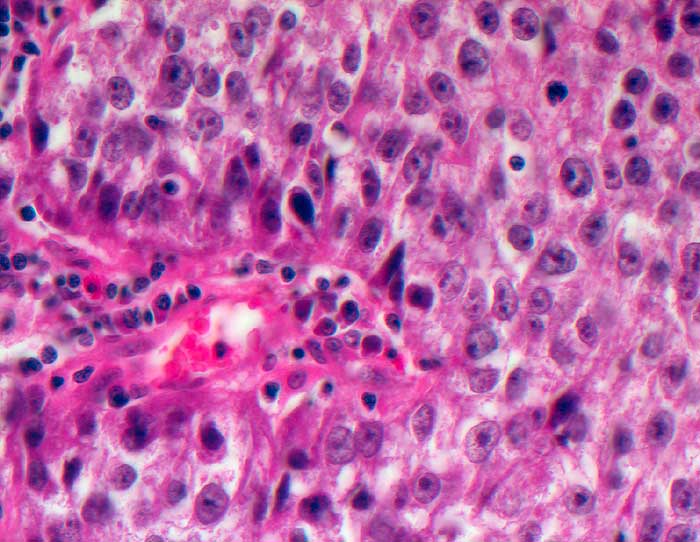

Die zytologische Diagnose des Prostatakarzinoms bereitet in der Regel keine grossen Schwierigkeiten. Die Karzinomzellen sind etwas grösser als normale Prostataepithelien. Die Kerne sind wenig grob strukturiert und ziemlich monomorph. Die Kern-Zytoplasma Relation ist erhöht. Nukleolen, die bereits bei 100 facher Vergrösserung gut sichtbar sind, stellen ein wichtiges Malignitätskriterium dar. Im Übrigen hängt das zytologische Bild von der Differenzierung des untersuchten Tumors ab.

Samenblasenepithelien können aufgrund ausgeprägter Atypien und manchmal erkennbaren Nukleolen mit Karzinomzellen verwechselt werden. Im Unterschied zu den Prostataepithelien enthält ihr Zytoplasma meist Lipofuszingranula.